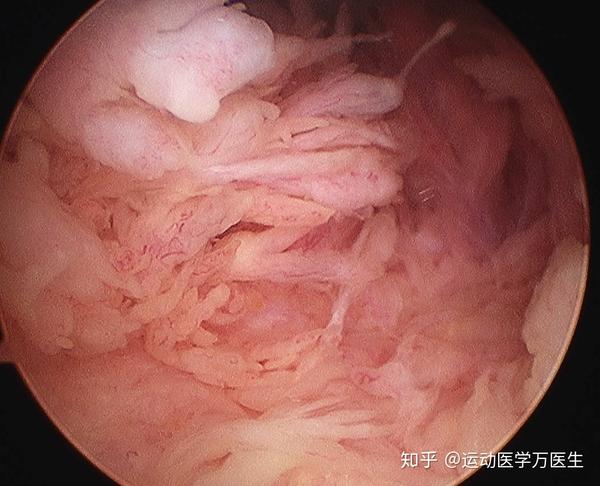

膝关节骨关节炎表现 治疗和常见误区有哪些 老中医张建福告诉你 每日头条

膝关节痛 医生说我得了滑膜炎 该怎么办 知乎